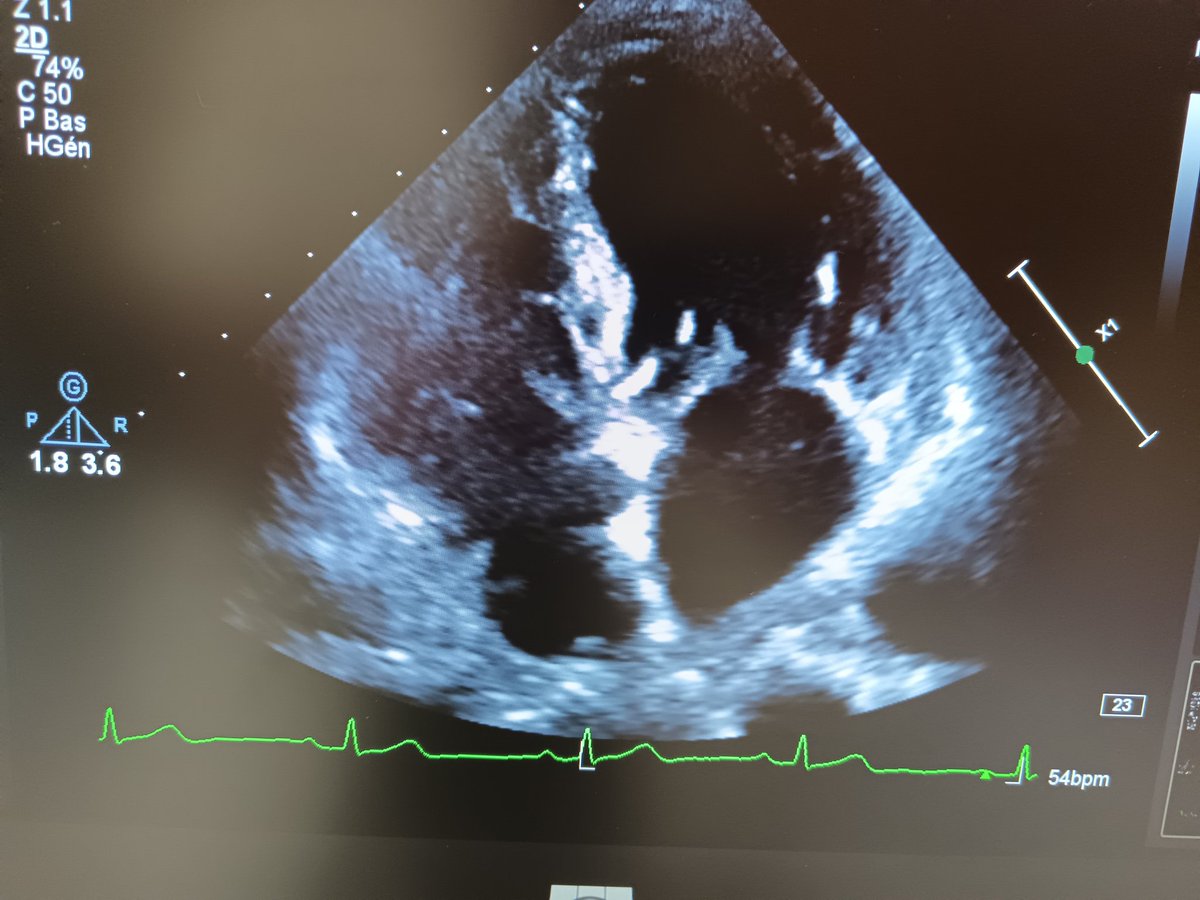

What do you think about these structural findings in the sub-mitral region ⁉️ @DrRajeshG1 @alex1708ander @argulian @lukasz_zydzik

FibrilloFlutter's tweet image. What do you think about these structural findings in the sub-mitral region ⁉️

@DrRajeshG1 @alex1708ander @argulian @lukasz_zydzik